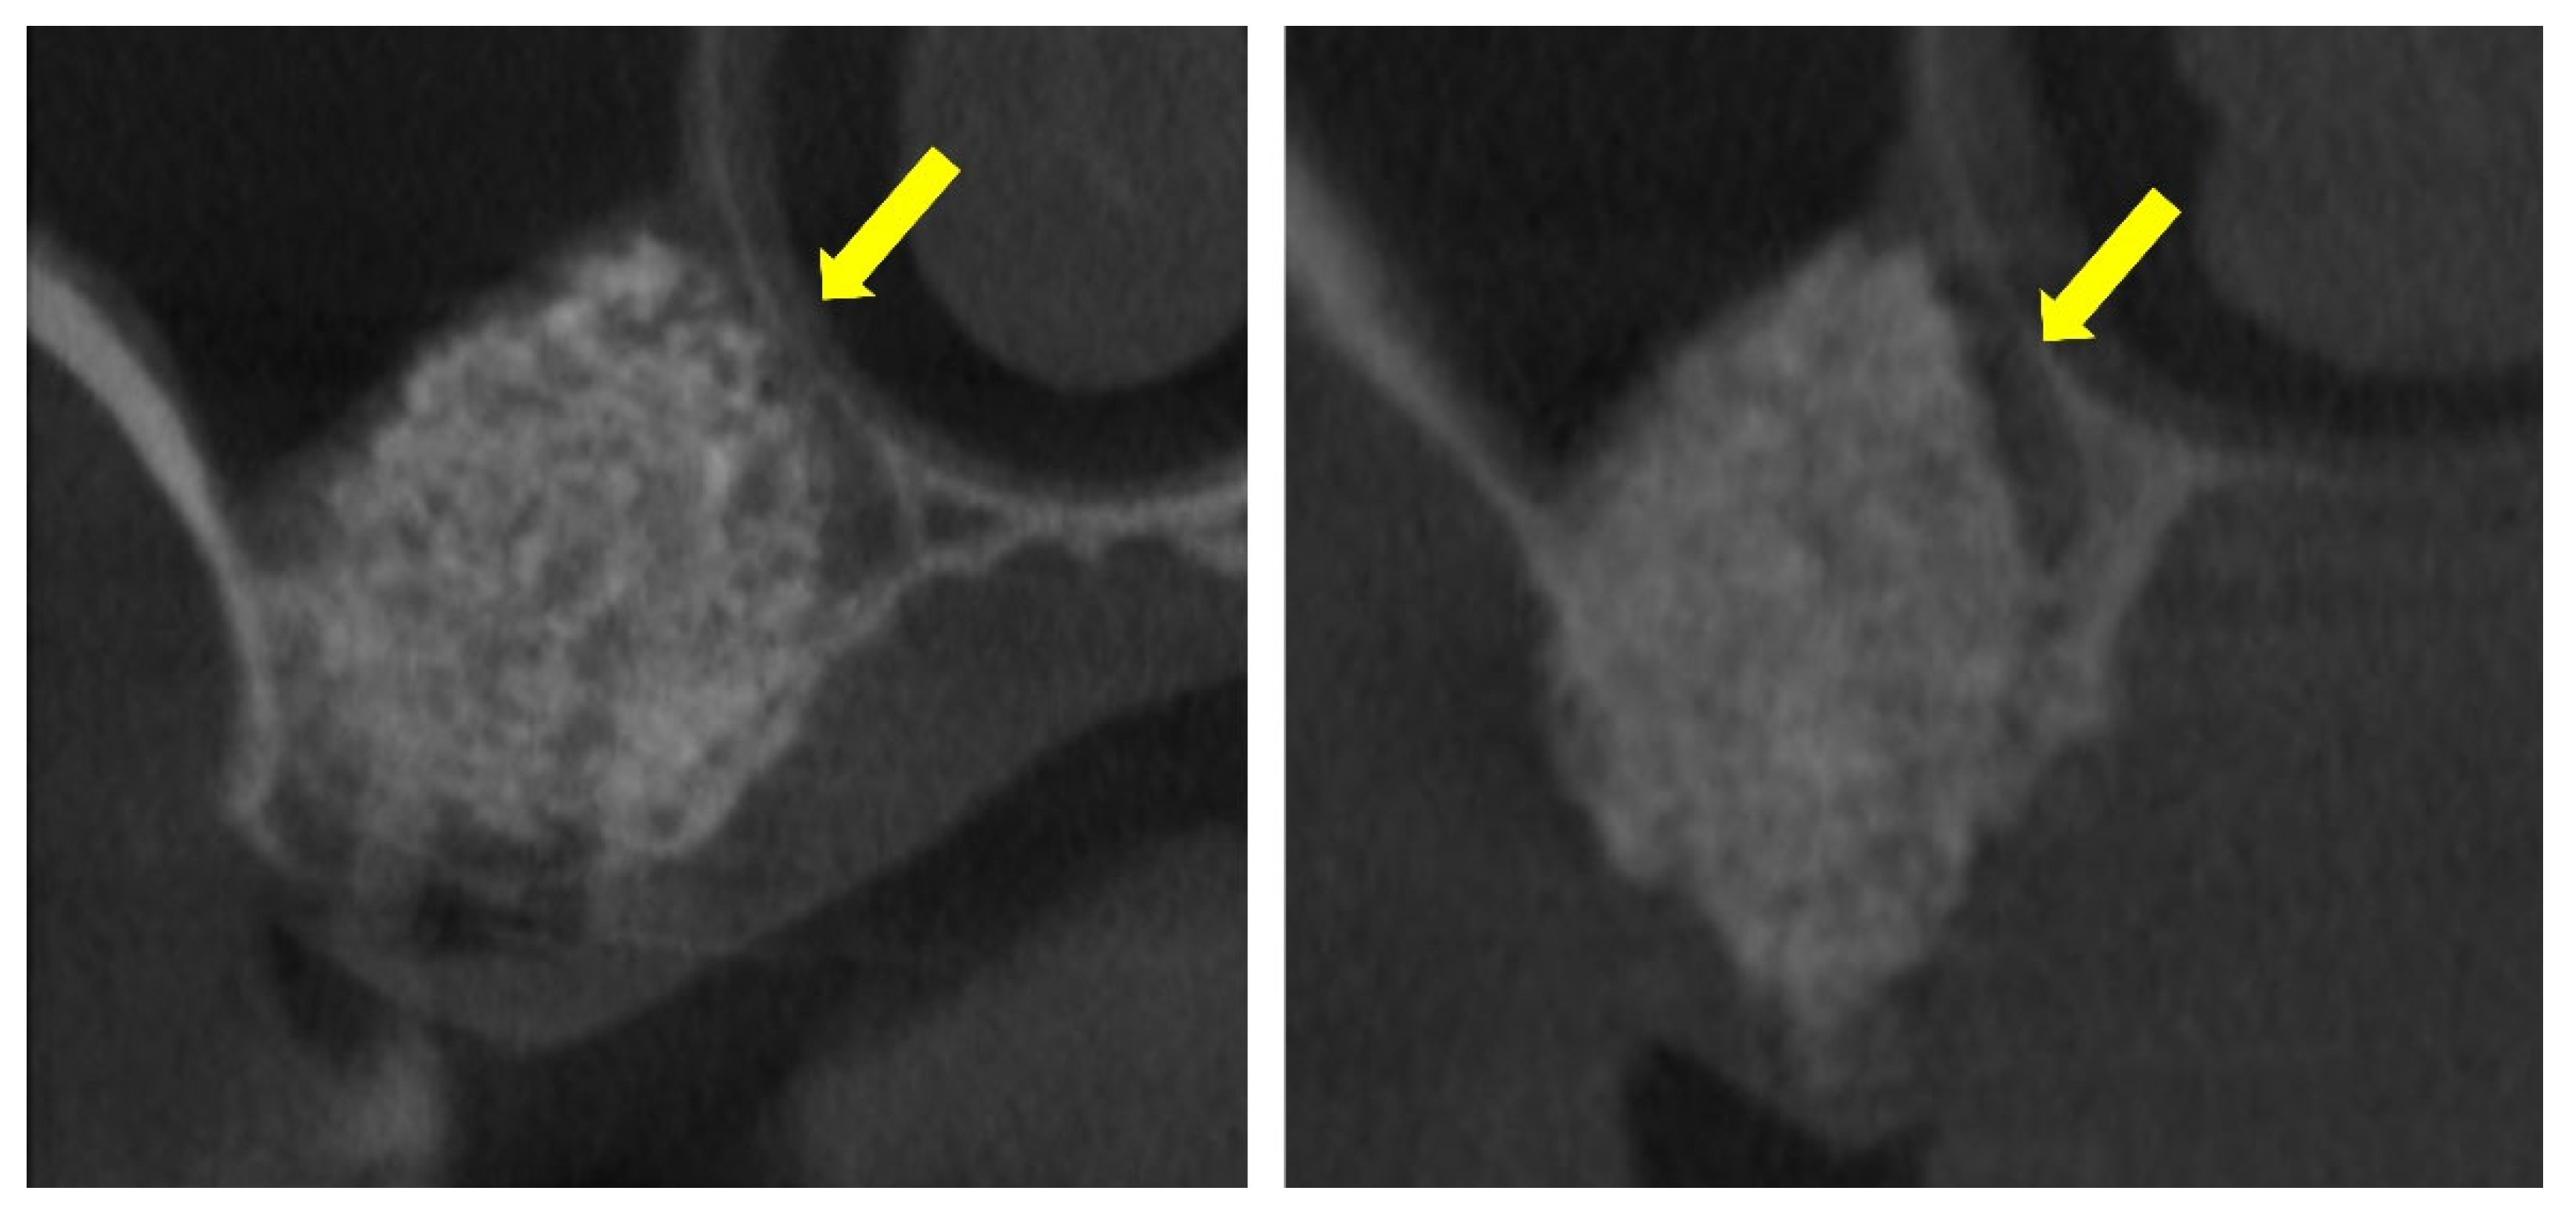

These prior studies, however, did not include a focused analysis of the interactions between the elevated and pristine sinus mucosae in cases where graft granules, positioned beneath the elevated mucosa, came into close proximity with the non-elevated mucosa (Figure 1).

Figure 1.

The elevated sinus mucosa is shown in direct contact with the pristine, non-elevated mucosa. The graft material appears closely positioned against the medial sinus wall, seemingly exerting pressure that maintains the two mucosal surfaces in close apposition (yellow arrows). This close apposition may contribute to the development of mucosal synechiae.